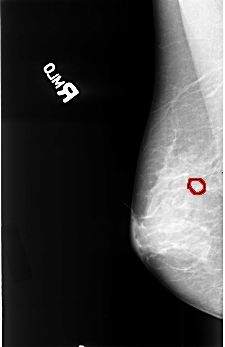

B_3389_1.LEFT_MLO

FILE: B_3389_1.RIGHT_MLO.OVERLAY

TOTAL_ABNORMALITIES 1

ABNORMALITY 1

LESION_TYPE CALCIFICATION TYPE PLEOMORPHIC DISTRIBUTION CLUSTERED

ASSESSMENT 4

SUBTLETY 4

PATHOLOGY MALIGNANT

TOTAL_OUTLINES 1

BOUNDARY